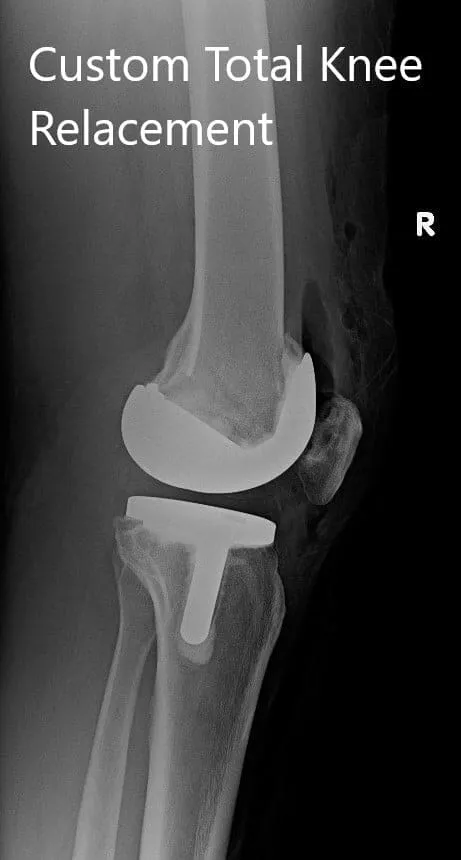

IMPLANTES UTILIZADOS: Fémur personalizado con tibia personalizada con inserto de polietileno de 10 mm y rótula de 32 mm x 6 mm.

Radiografía postoperatoria que muestra imágenes AP e laterales de la rodilla derecha